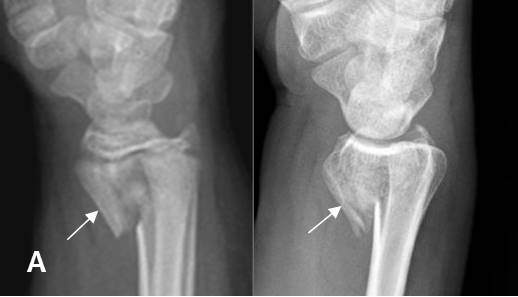

Fig 184. Fractura de Chauffeur.

A y B: Rx AP de muñeca. C: RM coronal en STIR. Fractura intra-articular y en sentido oblicuo, en la parte lateral del radio distal.